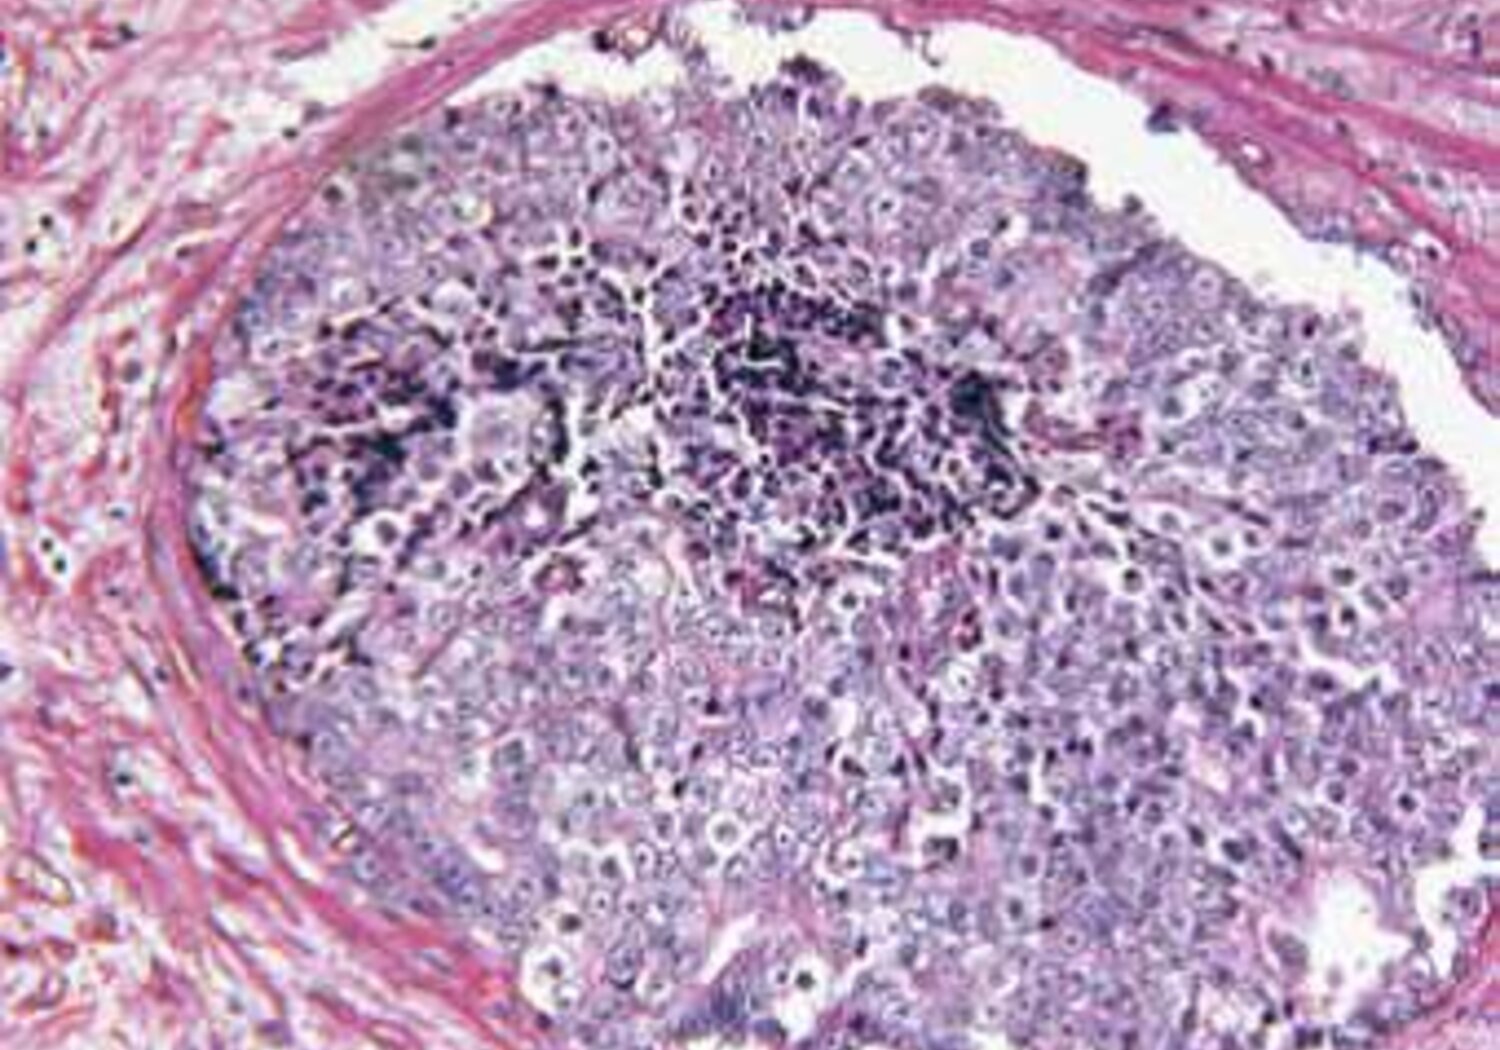

Molecular radiotherapy (MRT) specifically targets cancerous cells through the use of radioactive treatments that attach themselves to tumours in specific parts of the body, such as the liver. Currently, molecular radiotherapy is used in palliative care but it has the potential to become a first line treatment for cancer. Tailoring MRT for individual patients relies on accurately measuring the radioactivity of the drug and determining the therapeutic dose delivered to the tumour.

The EMRP project HLT11 Metrology for molecular radiotherapy successfully divided the radiation treatment process into a series of steps that could be related to primary standards, and developed methods for verifying the accuracy of each step. The project investigated the use of imaging techniques, to determine the dose delivered to the target tumour site.